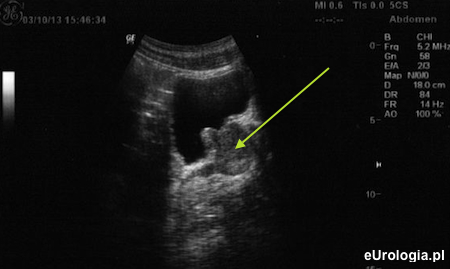

Badanie przezbrzuszne gruczołu krokowego (TAUS)

USG przezbrzuszne gruczołu krokowego wykonywane jest w celu oceny jego objętości i określenia objętości moczu zalegającego po mikcji. Badanie wykonywane jest głowicą do badań jamy brzusznej (głowica convex o częstotliwości od 3 - 5 MHz.

Fot. Obraz USG przezbrzusznego - przekrój strzałkowy. Gruczoł krokowy zaznaczony zieloną strzałką. Na zdjęciu widoczny jest płat środkowy (3 płat) wpuklający się do światła pęcherza moczowego.

Dokładna ocena echostruktury prostaty, ciągłości torebki i pęcherzyków nasiennych nie jest możliwa za pomocą przezbrzusznego USG. Podstawowym warunkiem oceny stercza w USG jest dobre wypełnienie pęcherza moczowego. Pacjenci przygotowani do badania USG prostaty przez powłoki brzuszne powinni powstrzymać się od oddawania moczu bezpośrednio przed badaniem. U pacjentów z założonym cewnikiem do pęcherza moczowego (cewnik Foley’a założony przez cewkę moczową lub cystostomię) zamyka się cewnik przed badaniem lub wypełnia pęcherz roztworem soli fizjologicznej. Po zakończeniu oceny gruczołu krokowego pacjent proszony jest o oddanie moczu, po którym ocenia się objętość zalegającego moczu w pęcherzu moczowym (PVR - Post-Void Residual).